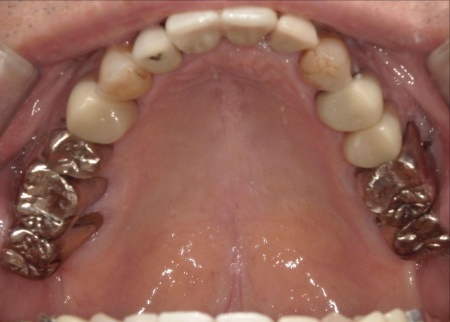

70代男性 右下奥歯を抜いてインプラント治療で噛み合わせを回復した症例

拝見したところ、右下奥歯(第2小臼歯)の周辺組織に炎症が広がり、歯茎が赤く腫れていました。

まず、右下奥歯(第2小臼歯)を抜き、骨が治癒するのを待ってから、インプラントを埋入します。

インプラントと顎の骨がしっかりと結合したら、精密な型取りを行い、インプラント上部に装着する最終的な被せ物を作製しました。

最後に完成した被せ物を装着し、見た目や噛み合わせに問題がないことを確認して、治療を終了しています。